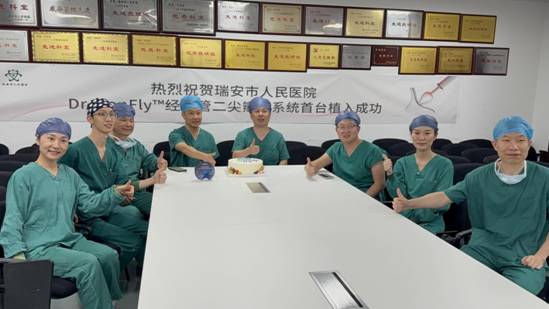

近日,瑞安市人民医院王永光、潘嘉西教授团队成功应用国产自主创研DragonFly™经导管二尖瓣夹系统,为一例P1脱垂伴部分腱索断裂的重度二尖瓣反流患者实施经导管缘对缘修复(TEER)手术。此次手术得到了浙江大学医学院附属第二医院王建安院士团队刘先宝教授与林心平教授的协助支持,双方术前开展了深入探讨,就技术理念、手术策略进行周密规划,并联手完成了一场高水平的TEER手术操作,整个植入过程仅用时40分钟,患者病症显著改善。手术成功亦标志着瑞安市人民医院在TEER领域取得了技术上的重要突破,有望在未来为更多患者提供更加优质的医疗服务。